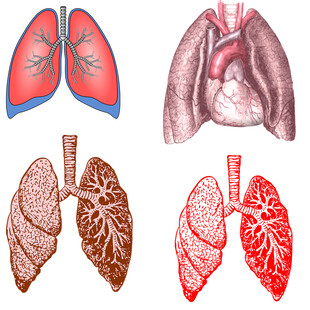

人体肺部解剖结构示意图 共享分:100

人体肺部解剖结构示意图 共享分:100 -

肺部结构与解剖示意图 共享分:100

肺部结构与解剖示意图 共享分:100 -

人体肺部解剖结构示意图 共享分:100

人体肺部解剖结构示意图 共享分:100 -